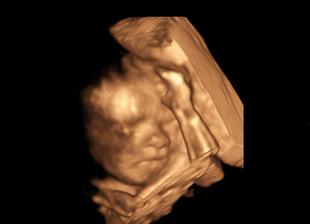

Nasa malinka v 24tt

juuujky. naadherne fotecky 🙂 my sme nakoniec na to 3d nesli, lebo malinka bola otocena ritkou k nam, do tvaricky by sme nevideli... ale takto nejak by vyzerala 🙂 len myslim, ze nostel by mala po rodicoch vacsi 😀

@bambulka12 toto ako sa ukazala bol chvilkovy zazrak....inak v kuse obe ruky na tvari 🙂

@bambulka12 a diky som zabudla 🙂 no doktor vravel, ze aspon na chvilku by mohla ruky dat prec a to tak dve minuty boli z celeho 3D 🙂